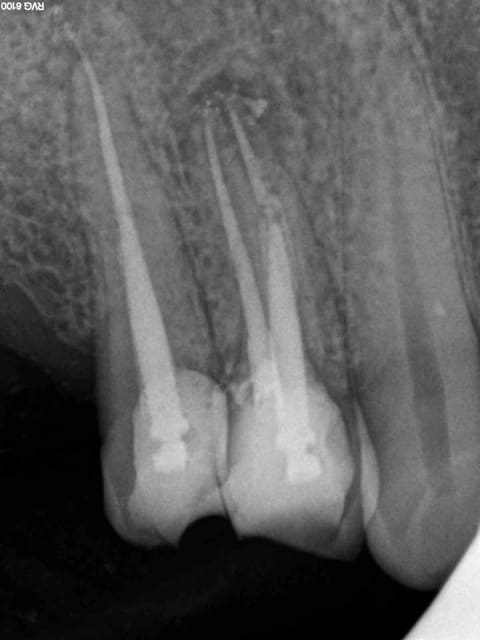

Aujourd'hui patient en urgence ca tombe bien pour une fois synchro avec un lapin.

45 mn de turbinage intensif 2 endos + 2 SC 33; On cote comment les radios ?

Z6, SC 20, Z3,Z3, SC20, Z3, Z3, SC 33, Z3, SC 33, Z3 ?